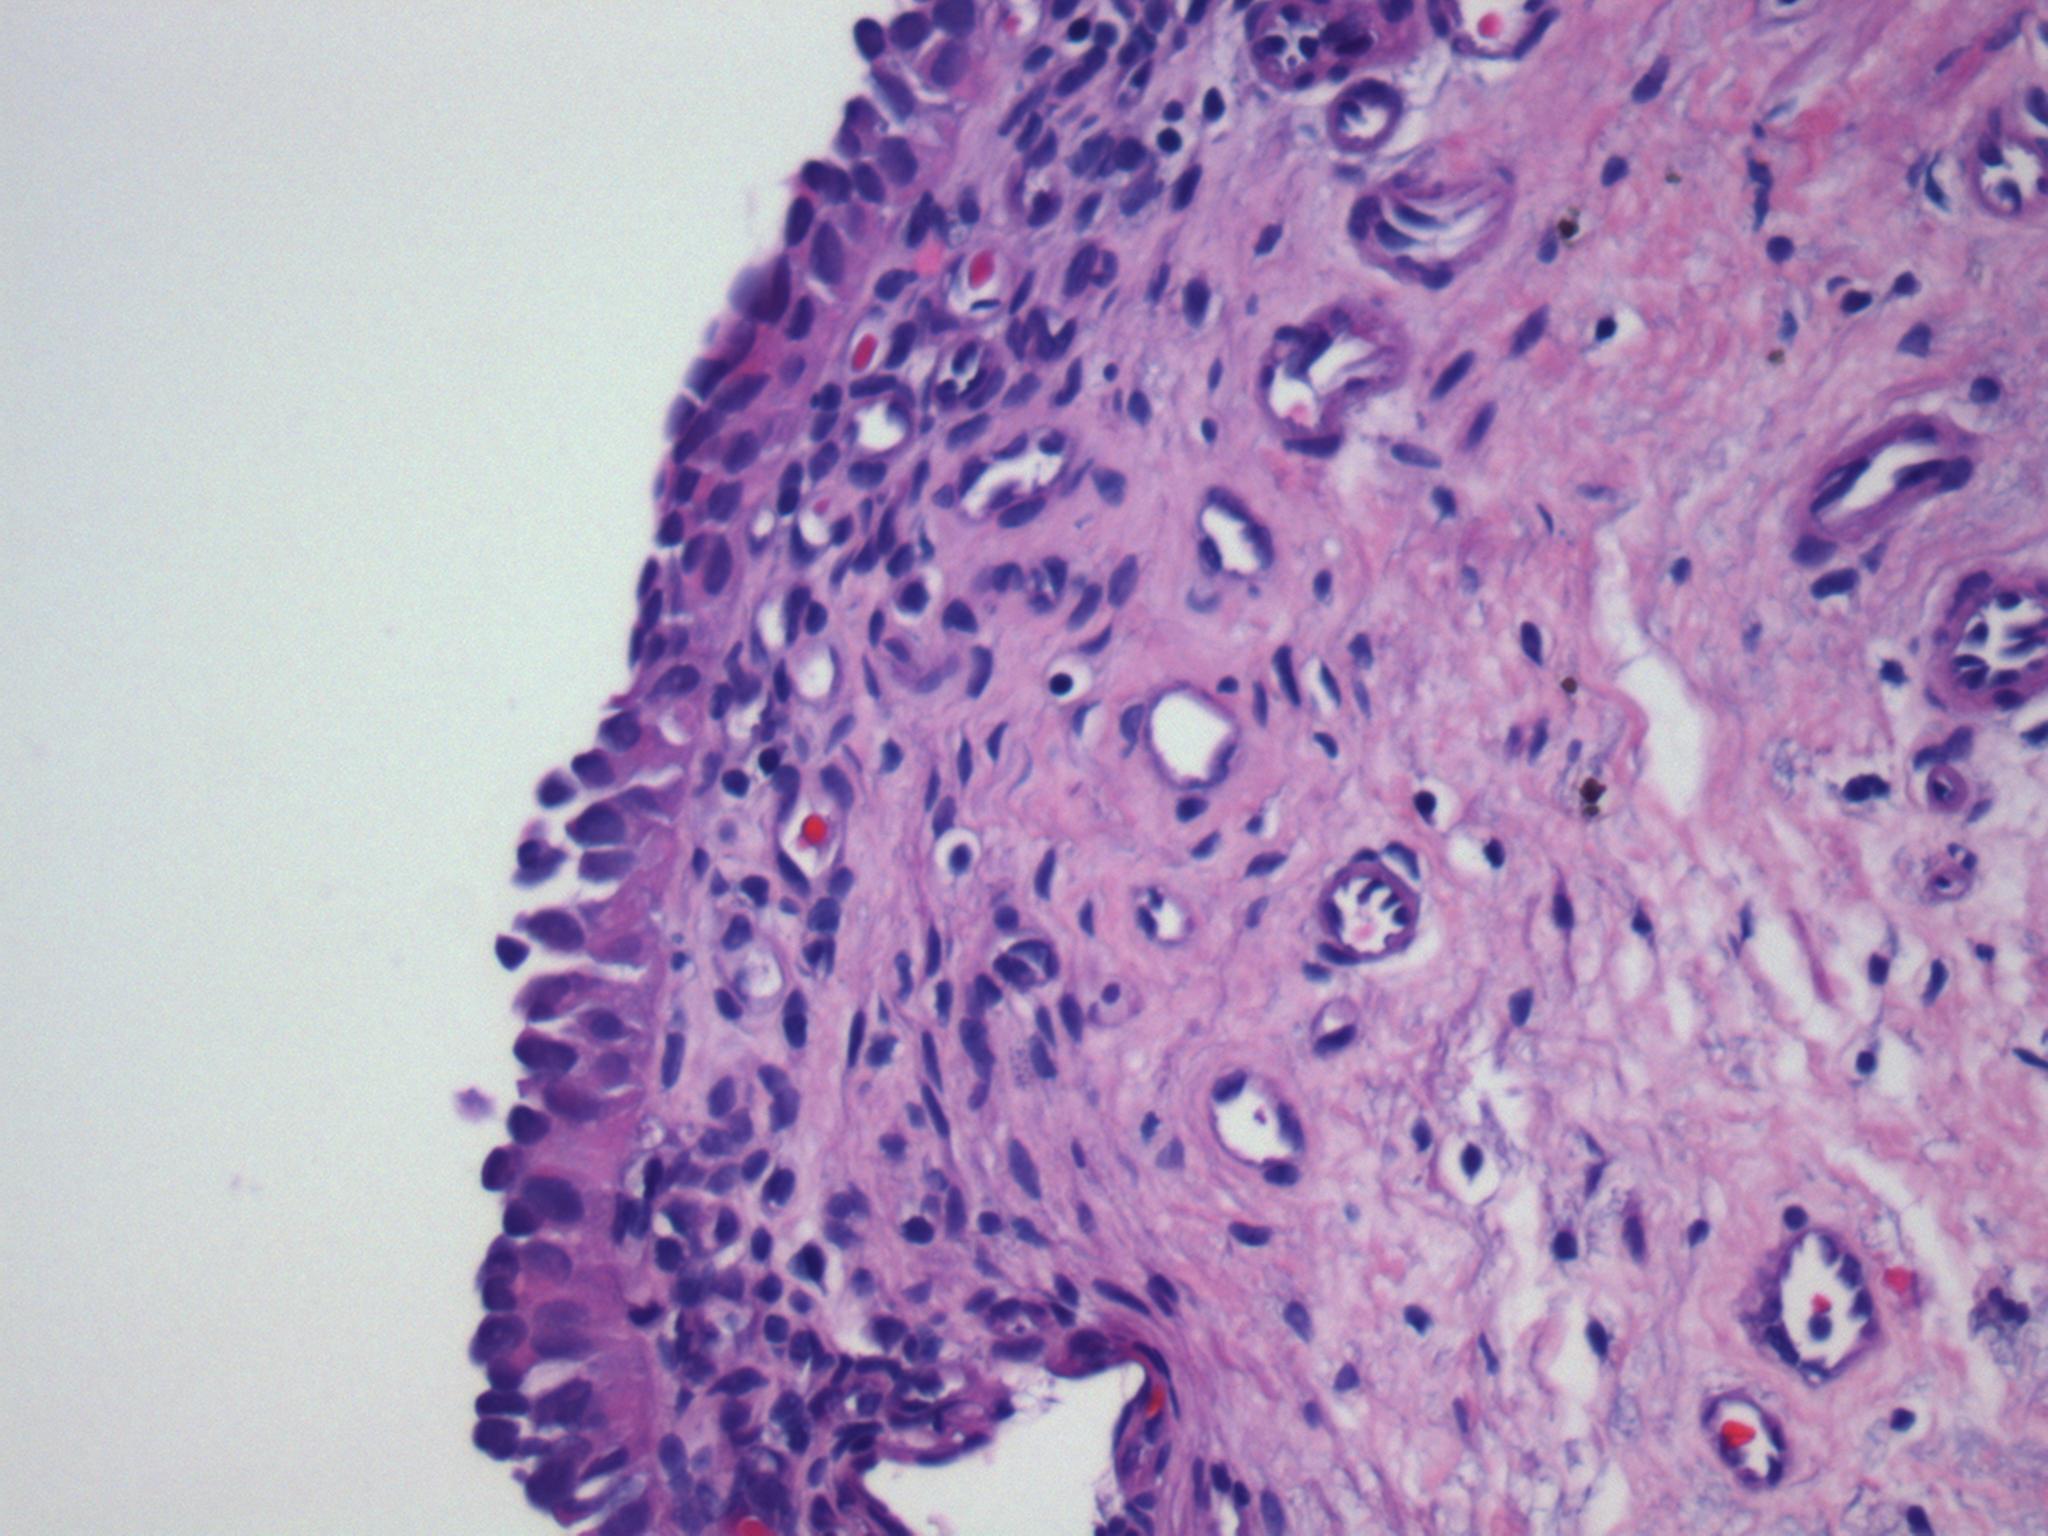

Consensus grade: Carcinoma in situ (CIS)

Prominent loss of cohesion of highly atypical urothelial cells